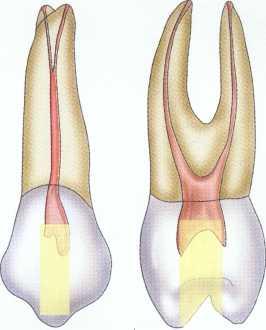

Maxillary Molars

Treatment of maxillary molars is never routine (Figure 2-22). In a recent study of maxillary first and second molars an MB2 canal was found in 96% of the mesiobuccal roots of maxillary first molars and 94% of the maxillary second molars. Approximately 54% were located in the traditional access opening, 31% were found with the use of a bur, and 10% were found with the aid of a microscope. The MBZ canal orifice was found on average 1.82 mm lingual to the main MB canal orifice.9 In another study of the maxillary first molar using microscopy, the MB Z canal was located in

93% of first molars and 60% of second molars4 (Figures 2-23 and 2-24). The difficulty in access, high percentage of fourth and even fifth canals, and root curvatures put even the "routine" maxillary molar in a high-risk category.3 Complicating factors such as limited opening, crowns, changes in tooth angulation, tooth position, and calcification make predictable treatment of these teeth challenging for even the most experienced clinician trained in microscopy, ultrasonics, and rotary instrumentation.

FIGURE 2-22 Buccal view of the access for maxillary molars.

FIGURE 2-23 An occlusal view of the access for maxillary molars.

Guidelines for canal location in the maxillary first molar (Figure 2-25) differ from that in the maxillary second molar. In the maxillary first molar the MB canal is located under the mesial buccal cusp (see Figure 2-25, D). The MBZ canal is located mesial to a line from the

MB canal toward the palatal canal (see Figures 2-25, E, and 2-26). The DB canal is located distal to the MB canal in the buccal groove area, slightly lingual to the MB canal (see Figure 2-25, G). The palatal canal is generally the largest canal and is located under the mesiolingual (ML) cusp (see Figure 2-25, F). These general locations remain the same as the pulp calcifies with age (Figure 2-27). Although these general principles apply to the maxillary second molar, the chamber may be narrower, resembling a straight line (see Fig. 2-55).